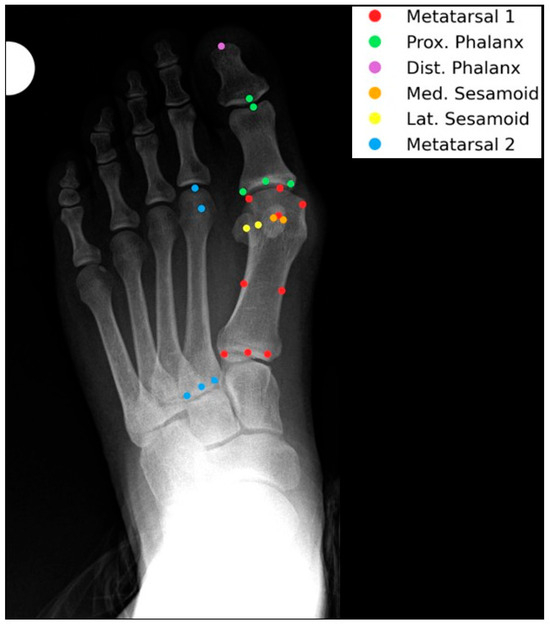

2.3. Landmark Annotation and Feature Extraction

- Color Scale: The gradient ranges from dark blue (−0.6) to dark red (0.6), indicating the strength and direction of correlation (negative to positive).

- Correlation Coefficients: Values are color-coded, with significant correlations (p < 0.05) highlighted. Notable ranges include r > 0.4 for HVA and IMA, and r > 0.3 for DMAA and HIA.

- Annotations: Specific distances (e.g., “2nd metatarsal head to proximal phalanx head,” “Medial sesamoid to proximal phalanx base”) are labeled to reflect anatomical relationships.